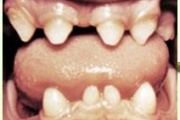

Puudub ülemine tsentraalne intsisiiv, kuid külgmised lõikehambad on juba lõikunud.

Turritavad ülemised lõikehambad.